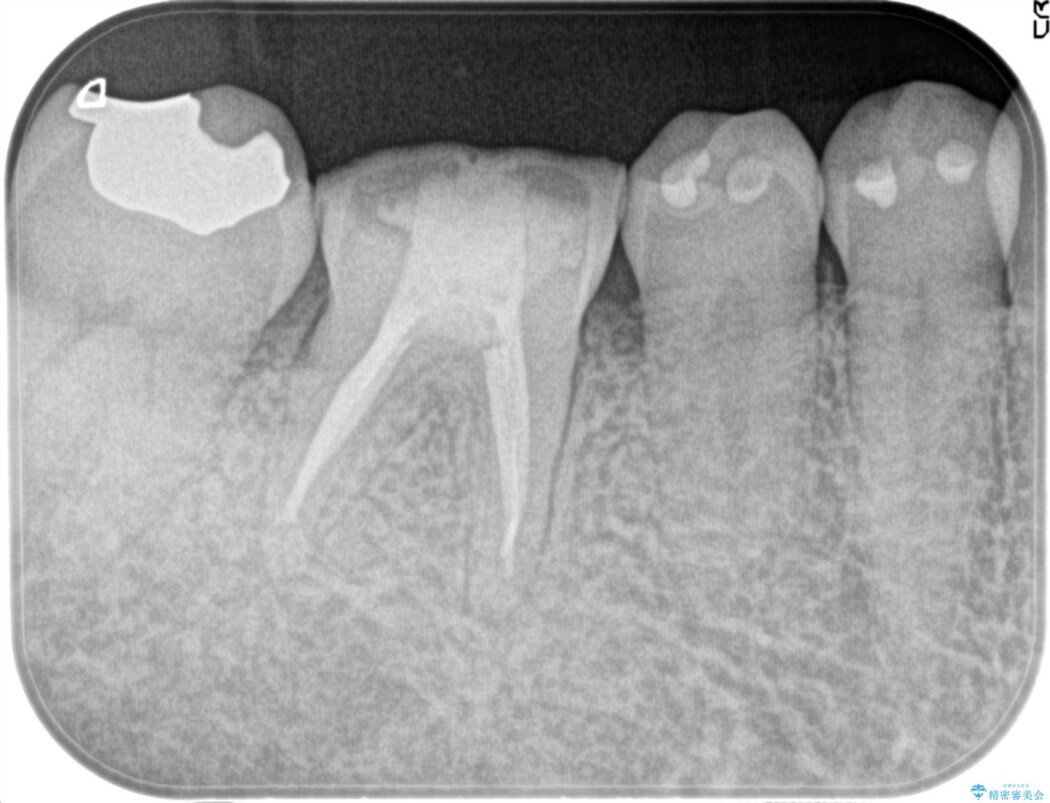

歯の内部にある神経(歯髄)の炎症を調べる検査を行い、痛みの原因となる歯を特定しました。

その結果、歯髄の炎症が進行し、痛みが生じる状態(症候性不可逆性歯髄炎)であると診断したため、精密根管治療の提案をしました。